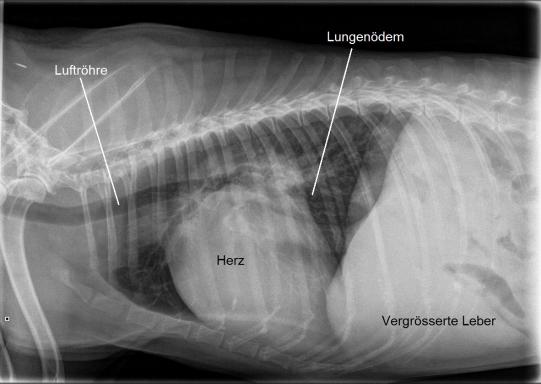

Beim Untersuch scheint der Hund deutlich älter als die angegebenen 6 Jahre und weist neben dem fortwährenden Husten ein deutliches Herzgeräusch und eine Herzrhythmusstörung auf. Das Bruströntgen zeigt ein generalisiert massiv vergrössertes Herz, eine vergrösserte Leber und ein leichtes Lungenödem; in einem zweiten Untersuchungsschritt zeigt ein EKG ein Vorhofflimmern mit einer folgenden Herzfrequenz von über 200 arrhythmischen Schlägen pro Minute, der Ultraschall massiv vergrösserte Herzkammern und nicht mehr korrekt schliessende Herzklappen, und zu allem Überfluss testet der Hund auch noch positiv auf Herzwürmer.

Ganz offensichtlich leidet Simon an einem massiven, weit fortgeschrittenen Herzproblem, welches trotz der schon zuvor verabreichten Medikamente nicht unter Kontrolle ist. Wir versuchen, mit diversen Medikamenten zur Unterstützung der Herz-Pumpfunktion, Kontrolle des Lungenödems und der Rhythmusstörung sowie Hustenbekämpfung das Problem einigermassen in den Griff zu bekommen.